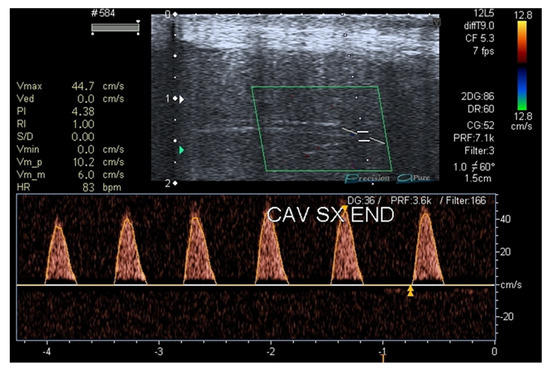

- Aversa, A.; Crafa, A.; Alessandra Greco, E.; Chiefari, E.; Brunetti, A.; La Vignera, S. The Penile Duplex Ultrasound: How and when to perform it? Andrology 2021, 9, 1457–1466. [Google Scholar] [CrossRef]